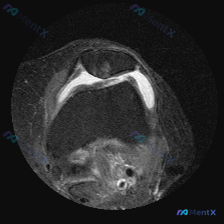

本次提供的是膝关节轴位MRI(T2WI/质子密度脂肪抑制序列),核心发现如下:

- 髌股关节:髌骨软骨面全层高信号改变,股骨滑车中央及内侧软骨也可见广泛高信号;髌股关节间隙可见明显高信号关节积液围绕髌骨

- 股骨远端:骨髓信号无明显异常水肿,皮质连续,无骨折

- 髁间窝:前交叉韧带走行区结构杂乱,条片状高信号混杂正常低信号,韧带张力和连续性显示不清

- 周围软组织:髌上囊及关节周围可见异常液体信号,提示广泛关节积液